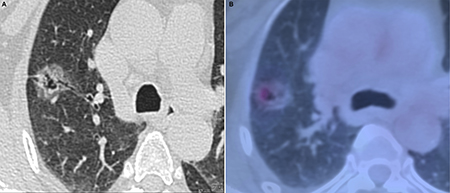

Figure 3: Invasive adenocarcinoma in 58-year-old woman. (A) transverse lung-window HRCT scan demonstrates a round, lobulated, well-defined subpleural mixed GGN with natural bronchus sign, cystic appearance, and pleural indentation in the apical segment of right upper lobe. (B) is caudal to (A): PET/CT fusion image with perfusion mode shows a 22.5-mm oval mixed GGN with 0.68 of CTR and 3.32 of SUVmax.